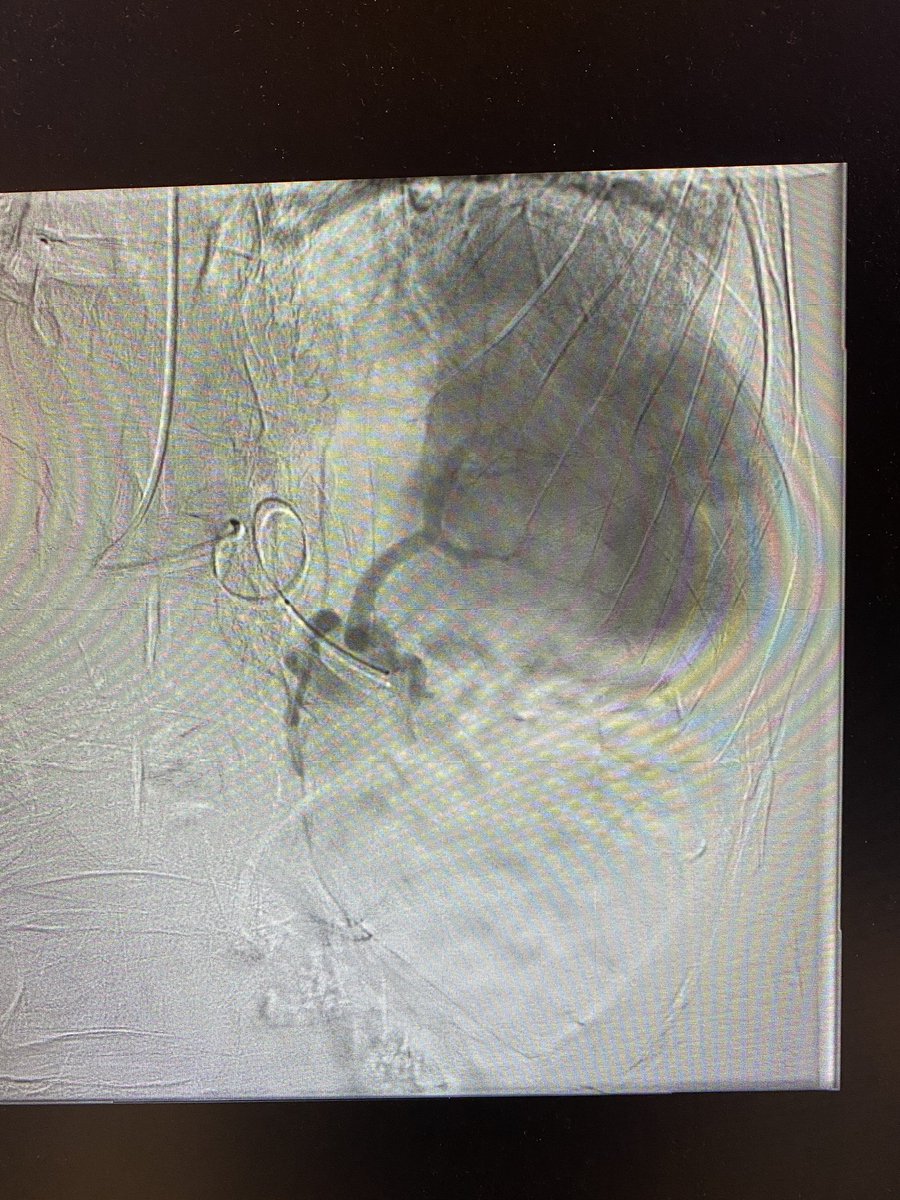

Malignant SVC syndrome w/ stridor; central upper extremity/IJ #DVT; @InariMedical FlowTriever for acute thrombus and ClotTriever for more than expected subacute/chronic; @BDandCo #Venovo for reconstruction @RonaldWinokurMD @TJUHospital @JeffersonRads @kekstero78 @carin_gonsalves